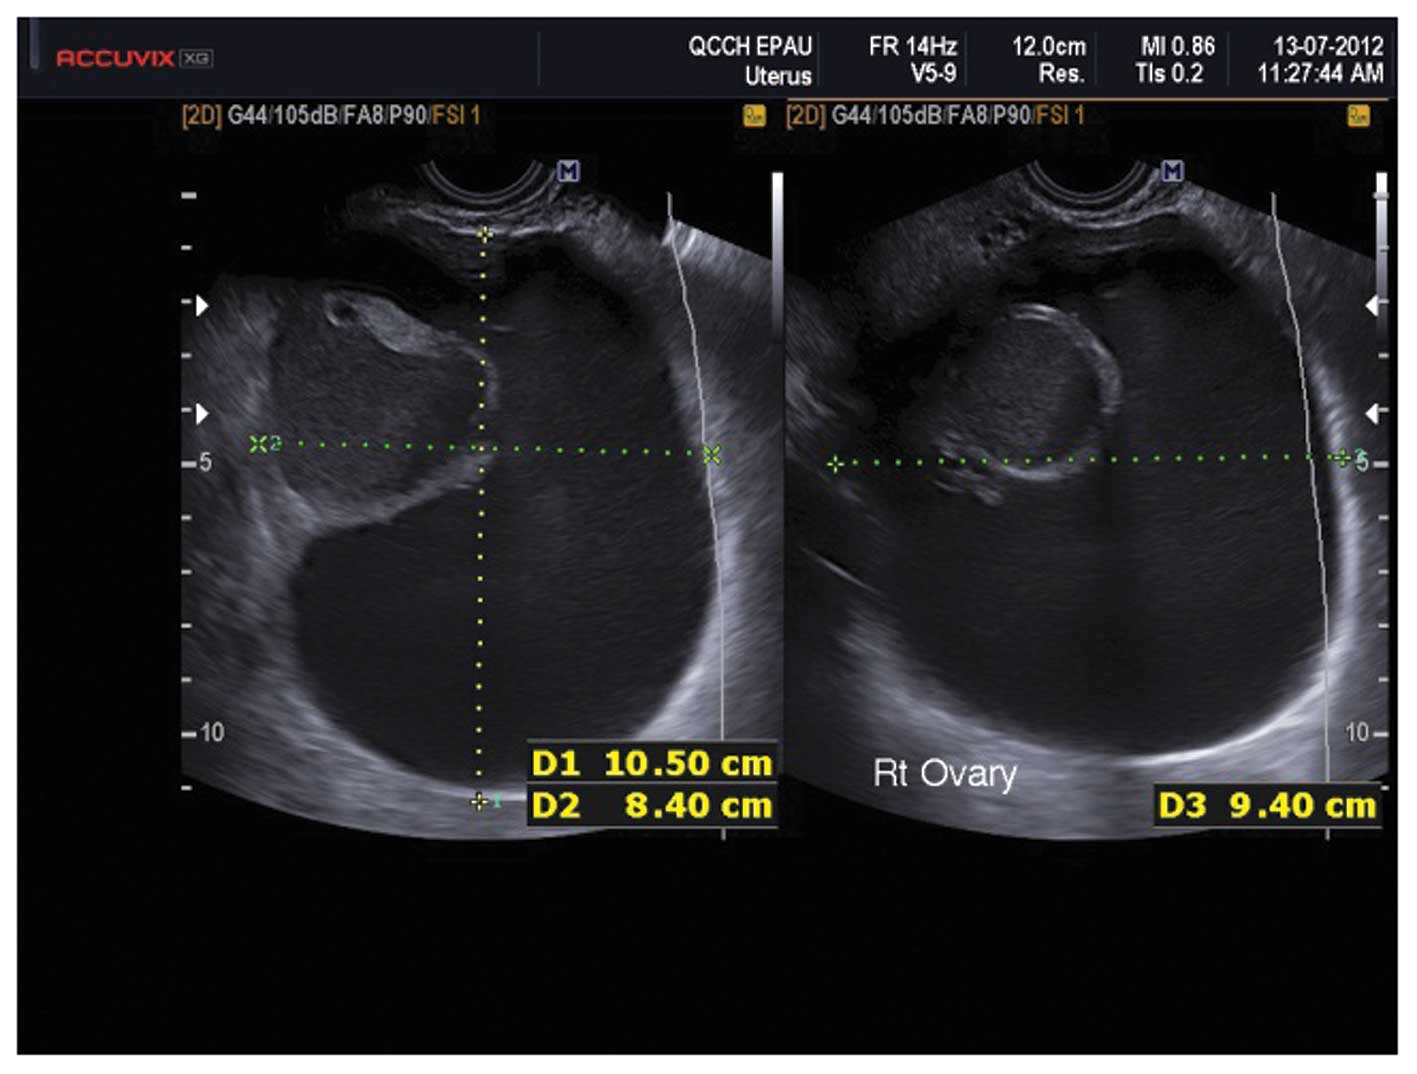

Mucinous cystadenomas

Mucinous cysts are classically thin walled, large and unilateral. They consist of internal thin-walled locules containing mucin which appears as fluid with low level echogenicity (25) (Fig. 11). In general neither serous nor mucinous cystadenomas are associated with significant vascularity (25).

Figure 11

Mucinous cystadenomas. (A) Unilocular. (B) Multilocular.

Caspi et al described the presence of variable echogenicity among different tumor locules as an ultrasound feature of multilocular mucinous cystadenomas (26) (Fig. 12), however this has not been confirmed in larger studies to date.

Figure 12

A mucinous cystadenoma with variable echogenicity among the cyst locules.